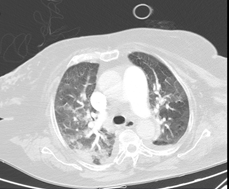

*Pulmonary CT angiography: No signs of PTE. Signs of PHT. Signs of hemodynamic decompensation with probable perihilar cardiogenic edema, bilateral pleural effusion and cardiomegaly (Figures 5 and 6).

Figure 5 Cardiomegaly. Bilateral pleural effusion.

Figure 6 No signs of PE.